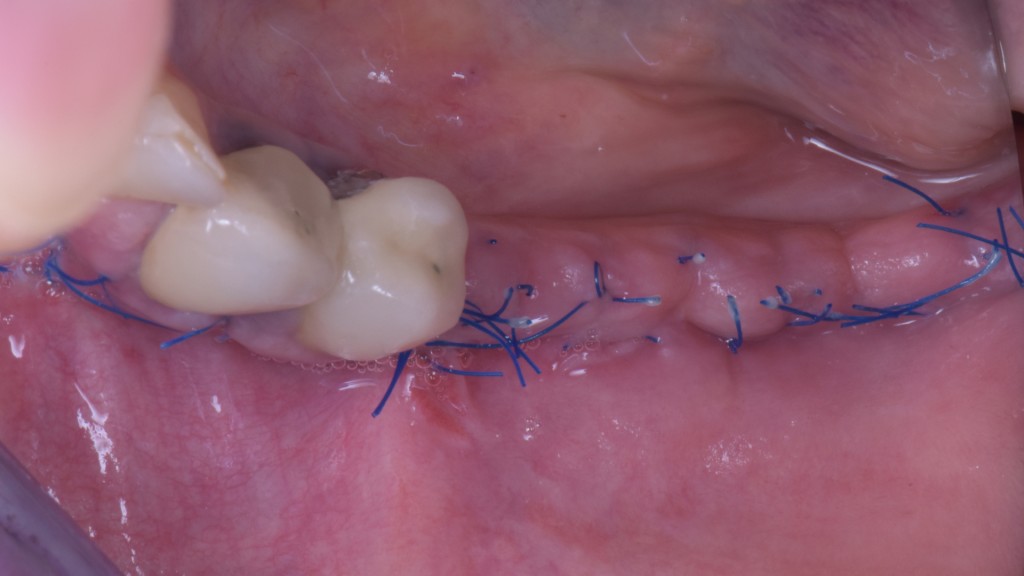

Se vuoi evitare latanto temuta ESPOSIZIONE non puoi suturare come cavolo ti pare. DEVI suturare così:

- Parti dallo scarico mesiale. Punti staccati, quello è facile.

- Sutura tutto il taglio con punti a materassaio orizzontale inserendo l’ago ad almeno 4 mm dal taglio.

- Chiudi poi i margini dei lembi con punti staccati tra un materassaio e l’altro.

Le guarigioni a quel punto saranno queste a 15 giorni. E’ difficile pensare che qui qualcosa possa esporsi… non credi??!!